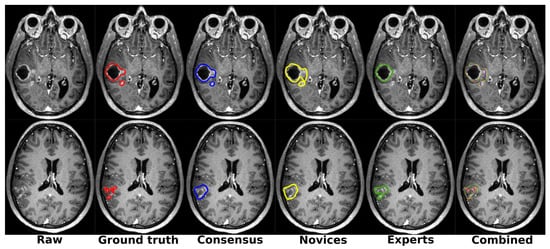

5.6. Inter-Rater Variability

| Arch. | Pre. | Ground Truth | Consensus | Novices | Experts | Total | Novices | Experts |

|---|---|---|---|---|---|---|---|---|

| nnU-Net | P1 | |||||||

| P2 | ||||||||

| AGU-Net | P1 | |||||||

| P2 |